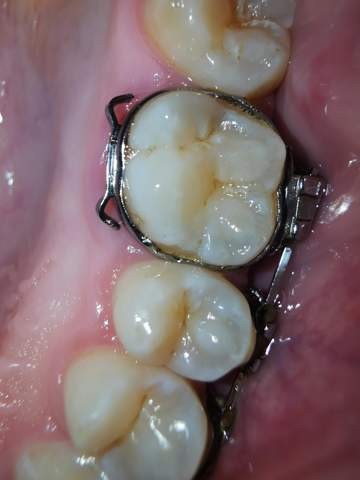

Seitliches Loch im letzten Backenzahn o Rechts hmm ich hab ein größeres Loch im letzten Backenzahn oben Rechts unzwar Seitlich zur Wange hin. Ich Baujahr 1995 habe furchtbare Angst vor dem Zahnarzt, obwohl ich selbst noch nicht wirklich schlecht Erfahrungen gemacht habe Ich habe bis 12Jahren etwa nur selten mir die Zähne geputzt, fast nur unter Zwang meiner Eltern Das denke ich heute noch Spuren hinterlassen, am oberen Ende hab ich Verfärbungen und (glaube) Belag Jetzt allerdings immer min 3mal täglich. Auch wenn Ihr Loch im Zahn von einem Zahnarzt behandelt wurde, kann nach einigen Jahren wieder eine Infektion auftreten!.